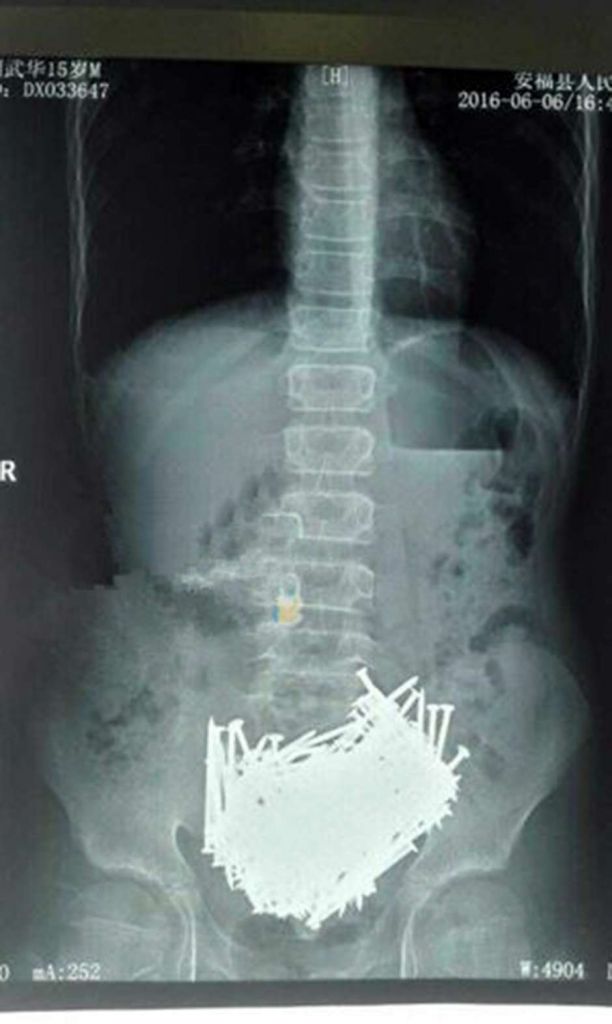

Médicos encontram 200 pregos em estômago de garoto na China

Lui, um garoto chinês de 15 anos, descobriu 200 pregos em seu corpo após se queixar de dores de estômago. As informações são do site inglês The Lad Bible .

Ao longo de meses, Lui engoliu pregos de metal, palitos, pedras e moedas graças a um distúrbio psicológico conhecido como pica, ou alotriofagia. Trata-se do apetite por substâncias não alimentares.

Os médicos fizeram tomografias computadorizadas no corpo do garoto e encontraram uma grande quantidade de pregos na boca do estômago.

Eles encaminharam Lui à emergência antes que os objetos causassem algum dano ao corpo do menino. Segundo relatos, mais de 200 pregos foram retirados do corpo de Lui, em um total de 700 gramas.